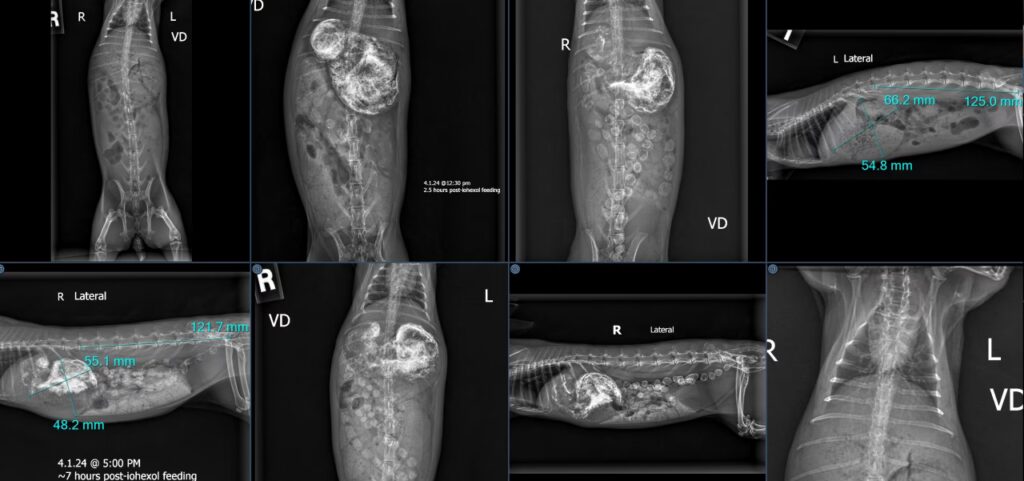

- Radiografías: Una radiografía abdominal es una herramienta diagnóstica muy útil. Permite visualizar la cantidad de gas y contenido en el estómago e intestinos, ayudar a diferenciar entre estasis funcional y una posible obstrucción física, y a veces identificar la causa subyacente (como problemas dentales o cálculos en la vejiga).